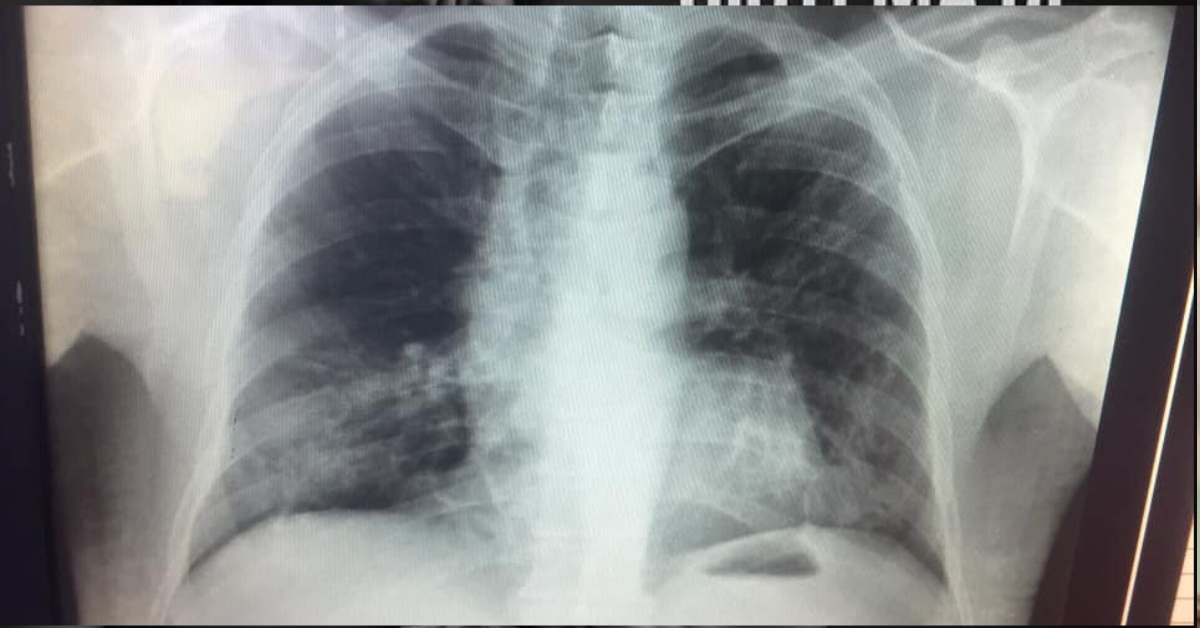

¿El resultado? Neumonía, bronquiolitis y una lesión en el pulmón derecho. Entonces sí corrieron. El bebé fue directo para terapia intensiva.